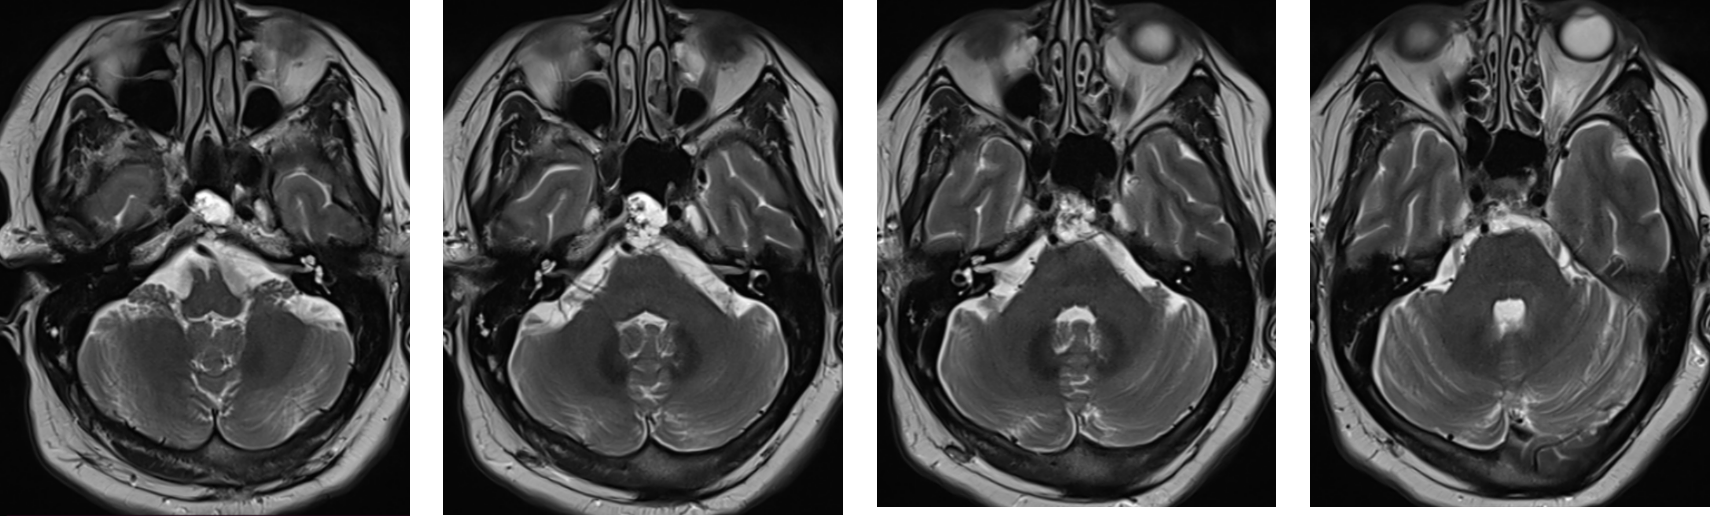

Figura 1: examinare IRM axial T2 se observă modificare de structură a clivusului cu prezența unor plaje cu semnal lichidian și de incluzii în hipersemnal T2 și FLAIR, hiposemnal T2 cu depășire posterioară a corticalei osoase.